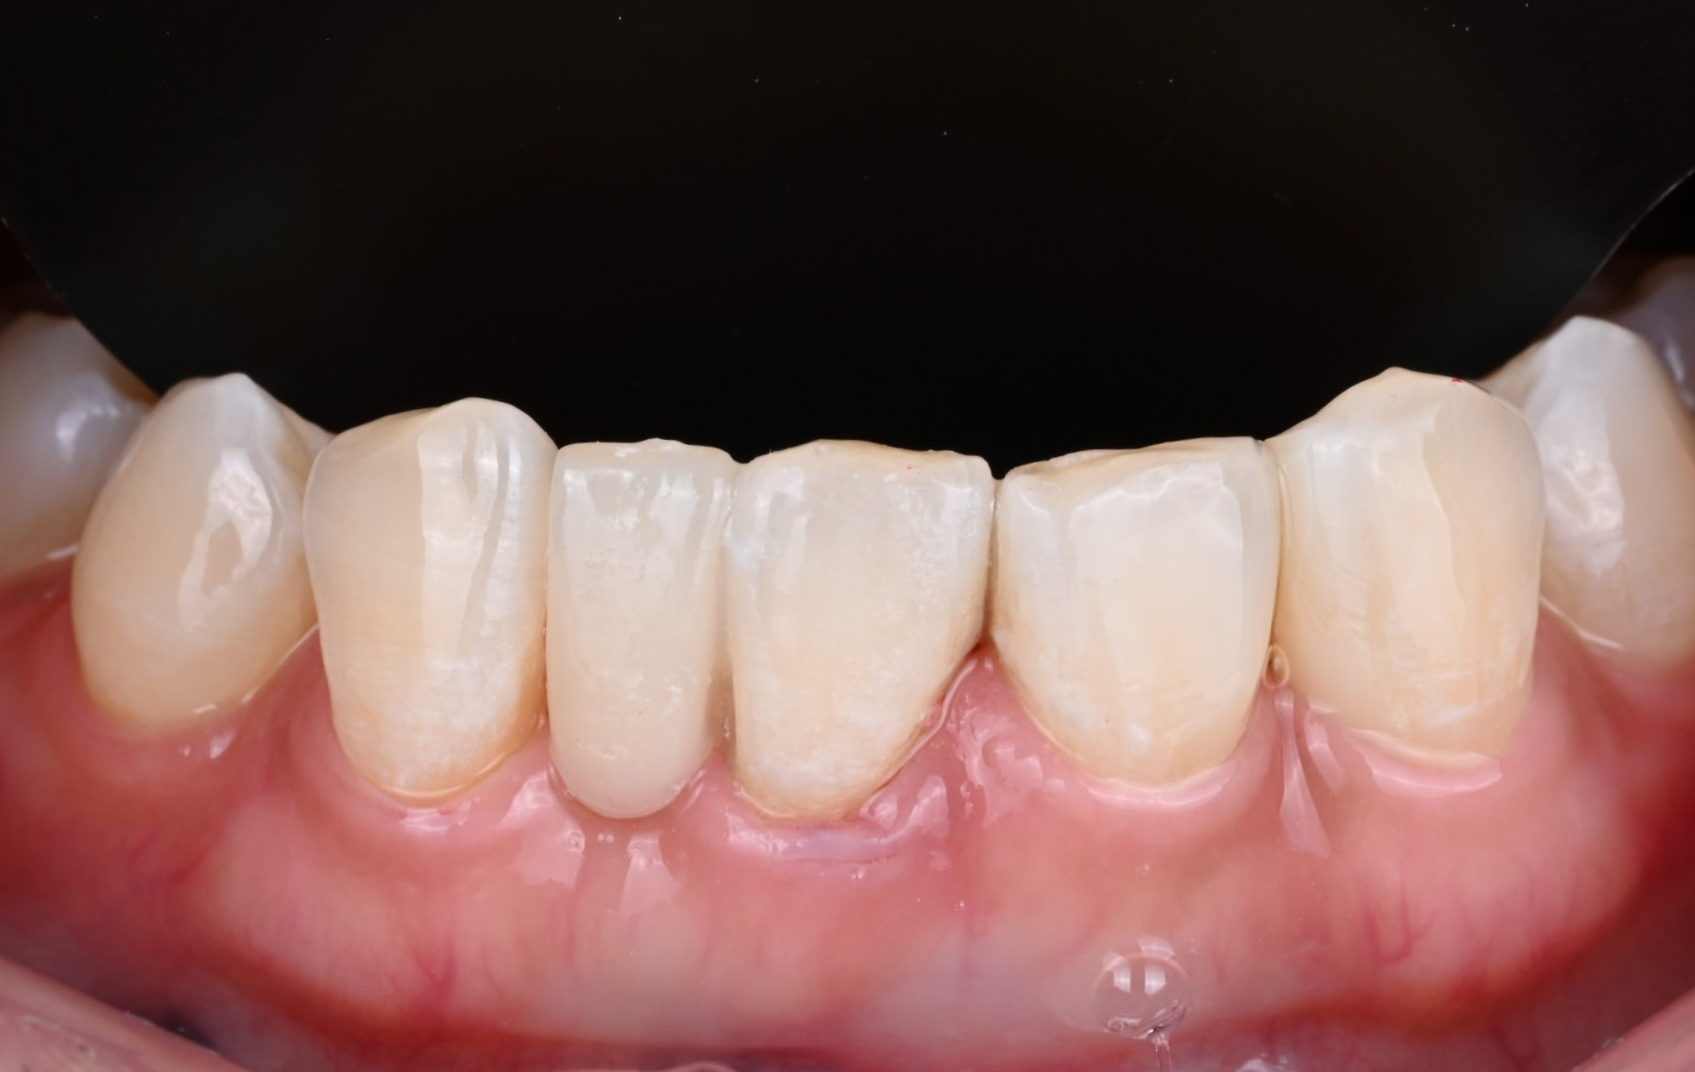

26.04.02 메릴랜드 브릿지 접착 후